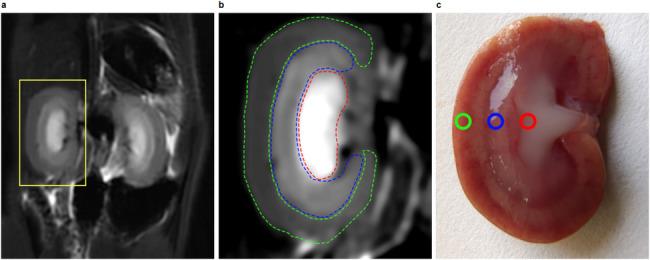

METHODS

In this study, forty-two male Sprague-Dawley (SD) rats were equally divided into two groups: a contrast media (CM) group and a control group, each containing 21 animals. The CM group was administered a tail vein injection of ioversol (370 mg I/ml, 1.5 ml/kg), while the control group received a saline solution in a similar volume. Assessments using IVIM-MRI and Doppler ultrasound were performed 24 h before and at 1, 24, 48, and 72 h post-injection. These assessments aimed to evaluate the true diffusion coefficient (D), pseudo-diffusion coefficient (D), perfusion fraction (f), apparent diffusion coefficient (ADC), and RRI. Concurrently, three rats from each group were sacrificed at these time points for renal histopathology, hypoxia-inducible factor-1α (HIF-1α) expression analysis, and the quantification of serum creatinine (SCr) and blood urea nitrogen (BUN) levels. Receiver operating characteristic (ROC) curves were plotted, and the area under the curve (AUC) was analyzed to evaluate the diagnostic performance of IVIM and RRI in predicting CIN.

Post-ioversol administration, significant declines were noted in the D, D, f, ADC across the renal cortex (CO), outer medulla (OM), and inner medulla (IM) from 1 to 48 h (P < 0.05), with the lowest values observed at 48 h. These parameters began to recover after 72 h. Conversely, RRI values escalated from 1 to 48 h, peaking at 48 h (P < 0.05), and then diminished gradually after 72 h. The control group showed no significant changes in these parameters. Furthermore, a negative correlation was observed between RRI, histopathological grades, HIF-1α expression levels, and the levels of SCr and BUN. In contrast, RRI exhibited a positive correlation with these pathological scores and the levels of SCr and BUN. ROC curve analysis revealed that the combined predictive performance of IVIM and RRI was superior to that of individual parameters.